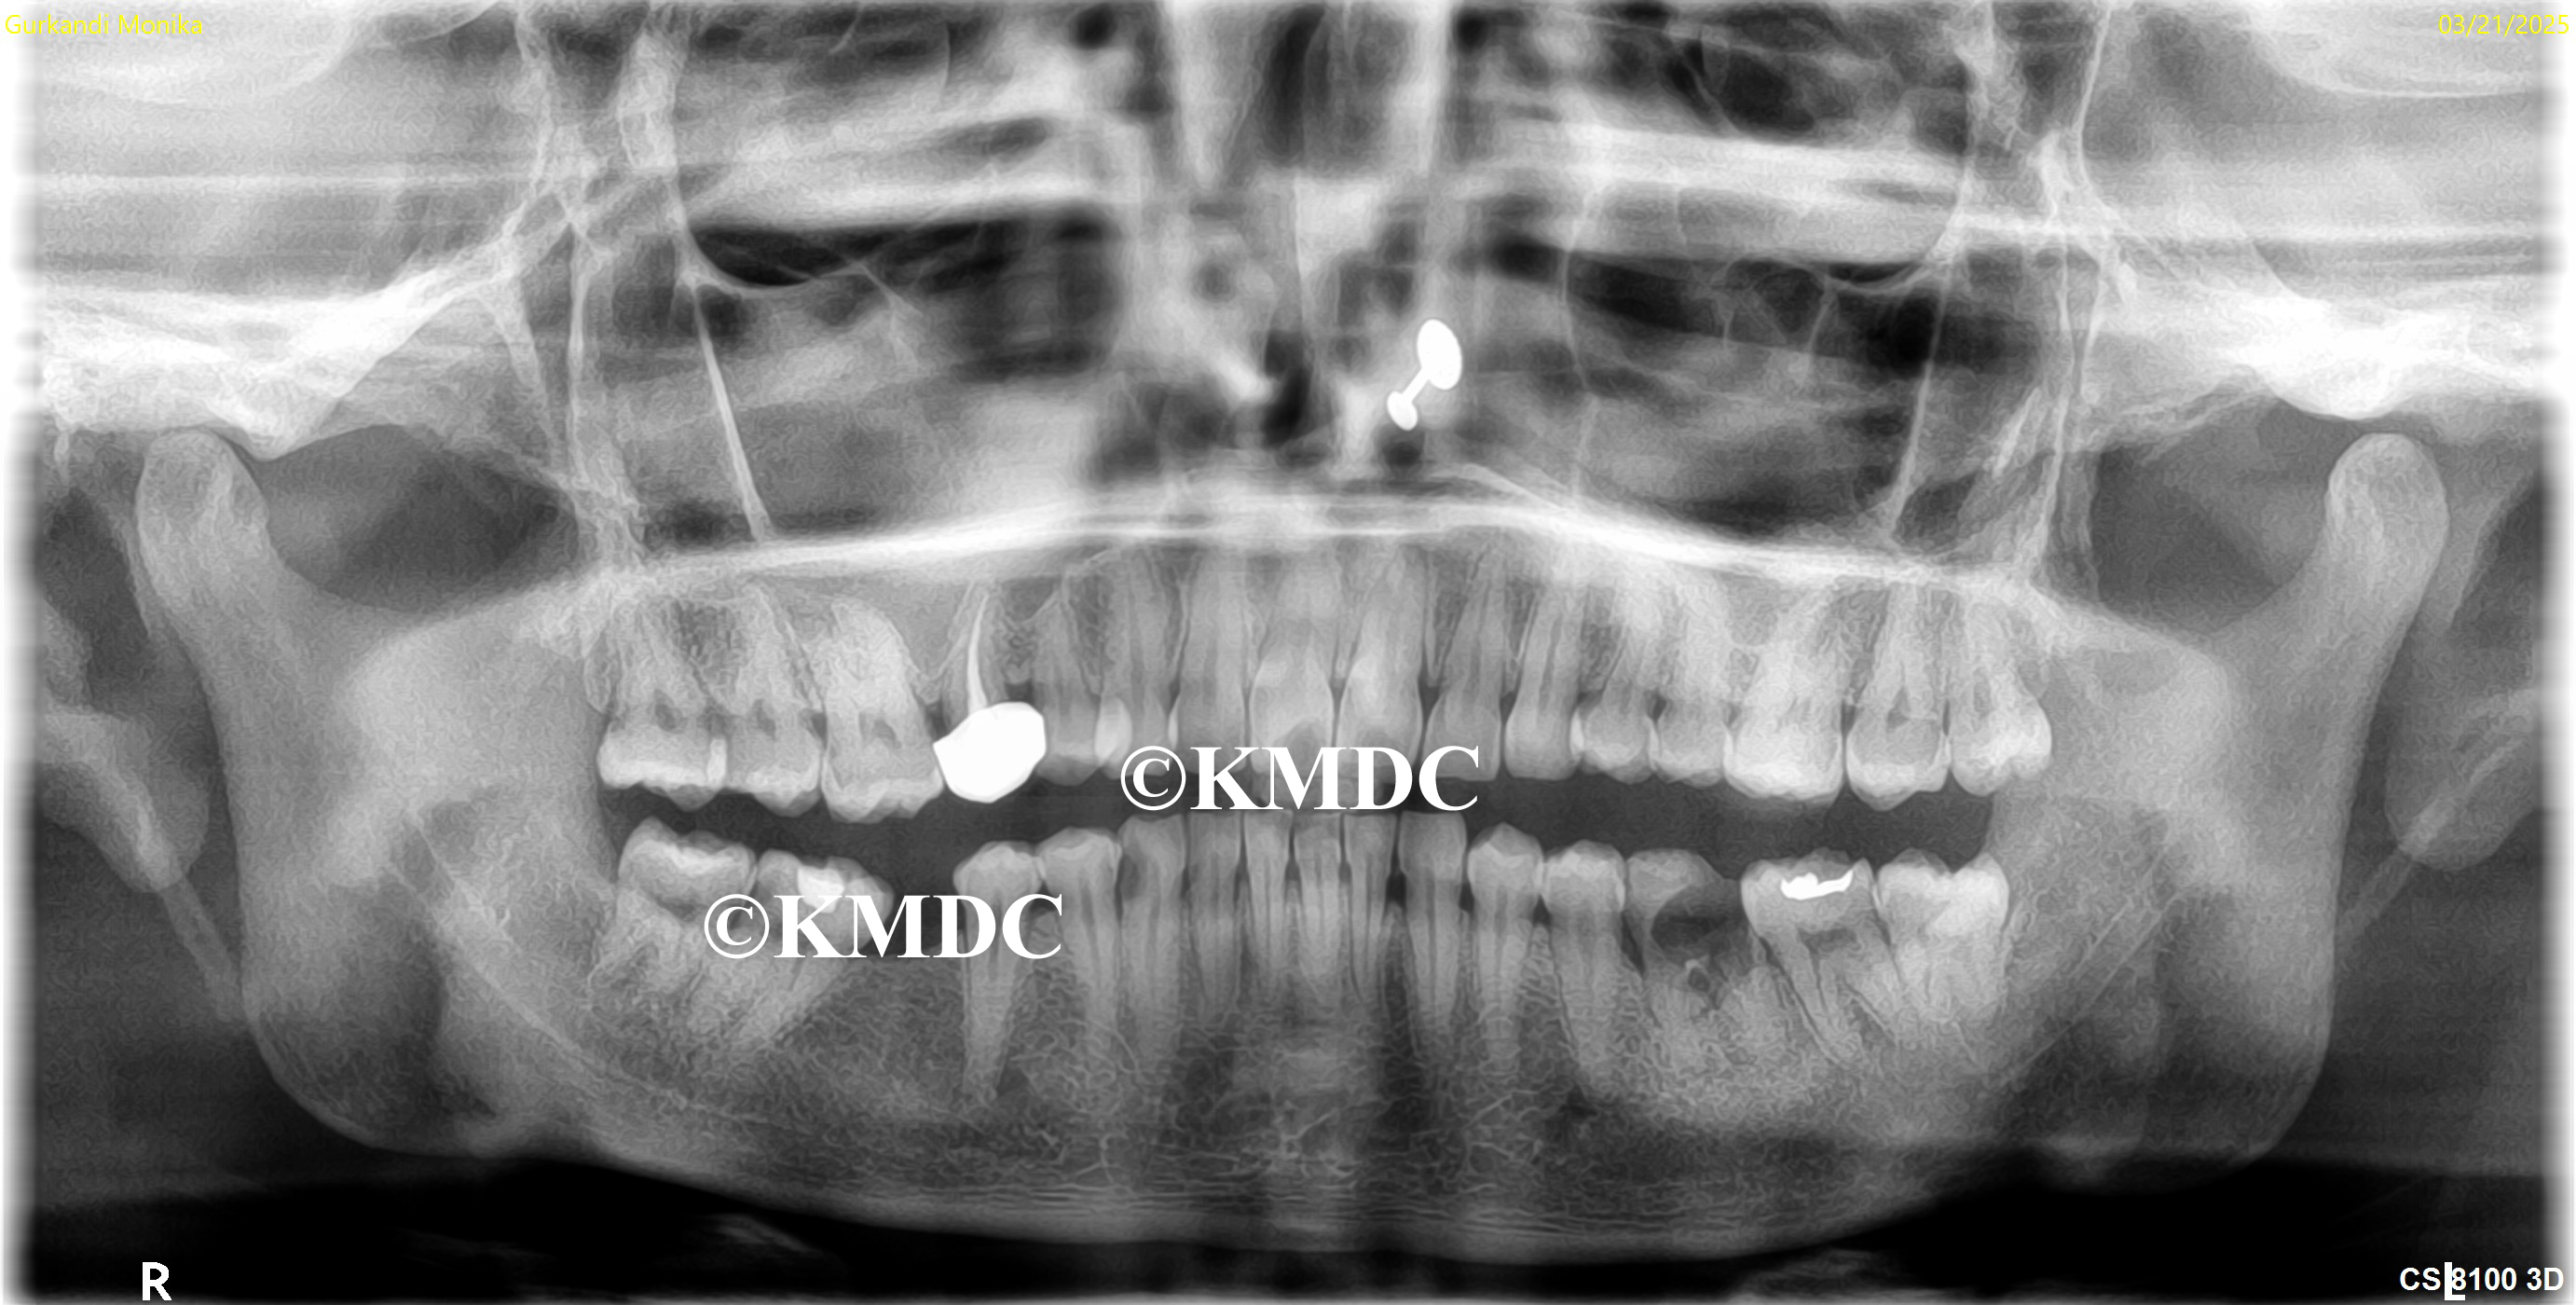

Clinical Gallery